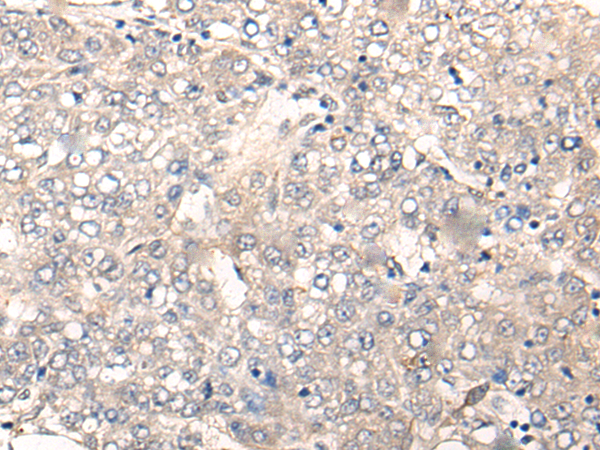

IHC positive control: |

Human liver cancer and human esophagus cancer |

IHC Recommend dilution: |

20-100 |